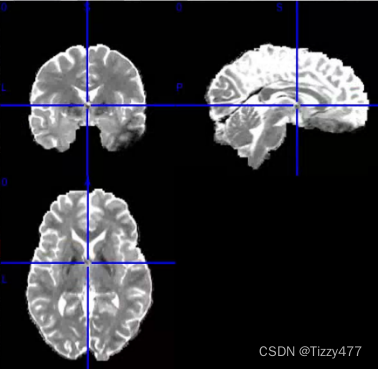

部分各向异性分数(fractional anisotropy, FA)

FA测量的是白质的完整性,指水分子各向异性成份占整个弥散张量的比例,它的变化范围从0-1。0代表弥散不受限制,比如脑脊液的 FA 值接近 0;对于非常规则的具有方向性的组织,其FA值大于0,例如大脑白质纤维 FA 值接近 1。

平均弥散率(mean diffusivity, MD)

MD反映分子整体的弥散水平和弥散阻力的整体情况。MD只表示弥散的大小,而与弥散的方向无关。MD 越大,组织内所含自由水分子则越多。